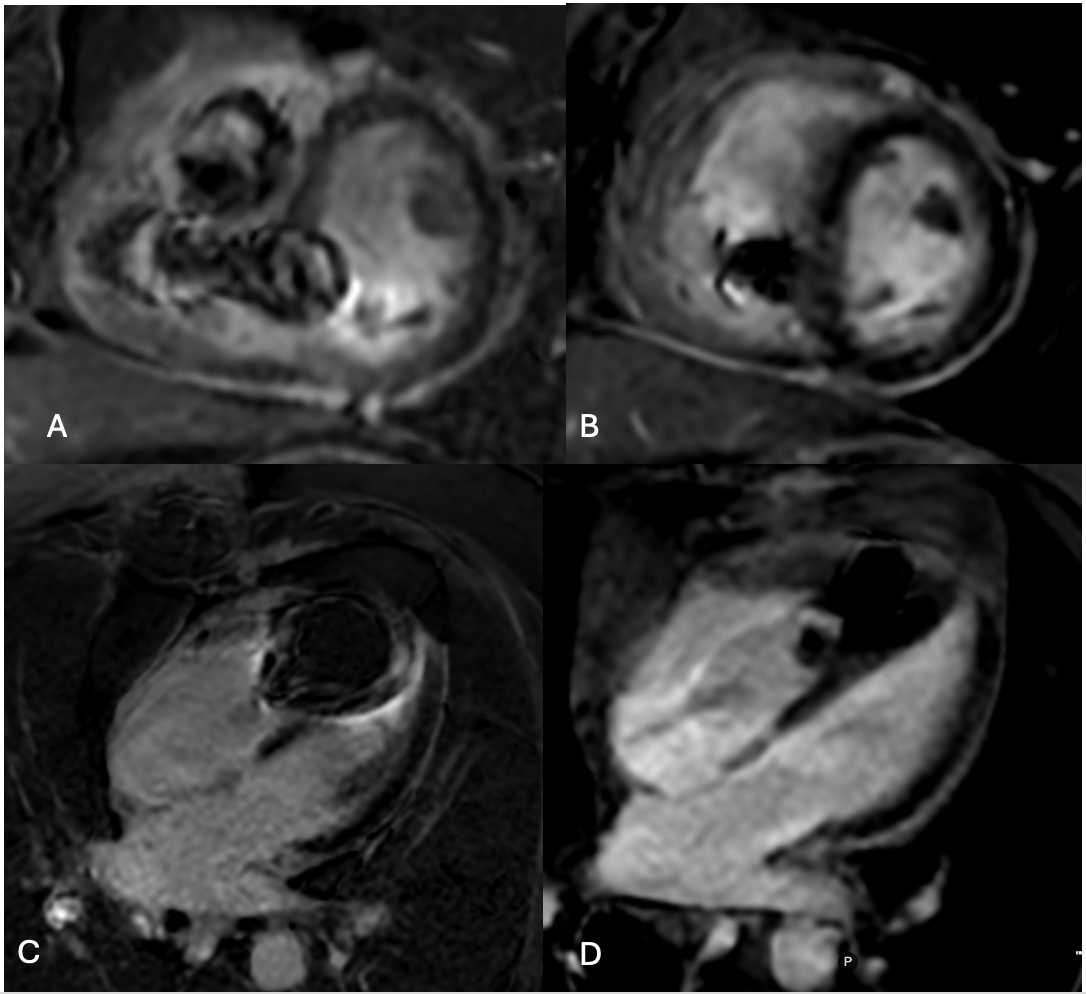

Figure 1 46-year-old male patient status post heart transplant with a right ventricular leadless pacemaker. (A, C). Conventional SSFP-based single-shot phase-sensitive LGE images in short-axis (A) and 4-chamber (C) views demonstrate significant artifact decreasing diagnostic confidence in the evaluation of the left ventricular septal myocardium. (B, D) SPGR-based single-shot phase-sensitive LGE in the short-axis (B) and 4-chamber (D) views demonstrate improved diagnostic confidence in evaluation of the left ventricular septal myocardium.